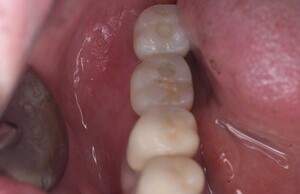

インプラント治療の症例2

口腔内写真

- Befor

- After

| 年齢 | 50代・男性 |

|---|---|

| 主訴 | 左上7番 左下5番7番 |

| 治療内容 | ・インプラント埋入 ※1:GBR(骨造成)・・・骨再生誘導法。骨の高さや厚みを人工骨や人工膜などを使用し再生する方法 |

| 治療費 | 合計:1,809,500円(税込) ■内訳 ・左上7番 ・左下5番7番 |

| 治療期間 | 左上7番約1年 左下5番7番約10ヵ月 |

| 治療方針 | 左上7番は昔他院で被せものをしており、被せものの中が歯ぐきの中まで虫歯になっていたため抜歯せざるを得ない状態だった。抜歯と同時に骨造成を行い、骨が出来るまで4ヵ月待ってからインプラントを埋入した。 ※2ポンティック・・・歯のない部分を補うダミーの歯。 |

| 担当者所見 | 元々金属の被せものが多く入っていたため、2次カリエス※3が多かった。今回は金属ではなく、ジルコニアを使用し、2次カリエスにならないよう、患者様にはブラッシング指導とメンテナンスの重要性をお伝えした。 ※3二次カリエス・・・詰め物や被せものを入れた歯が虫歯になること。 |